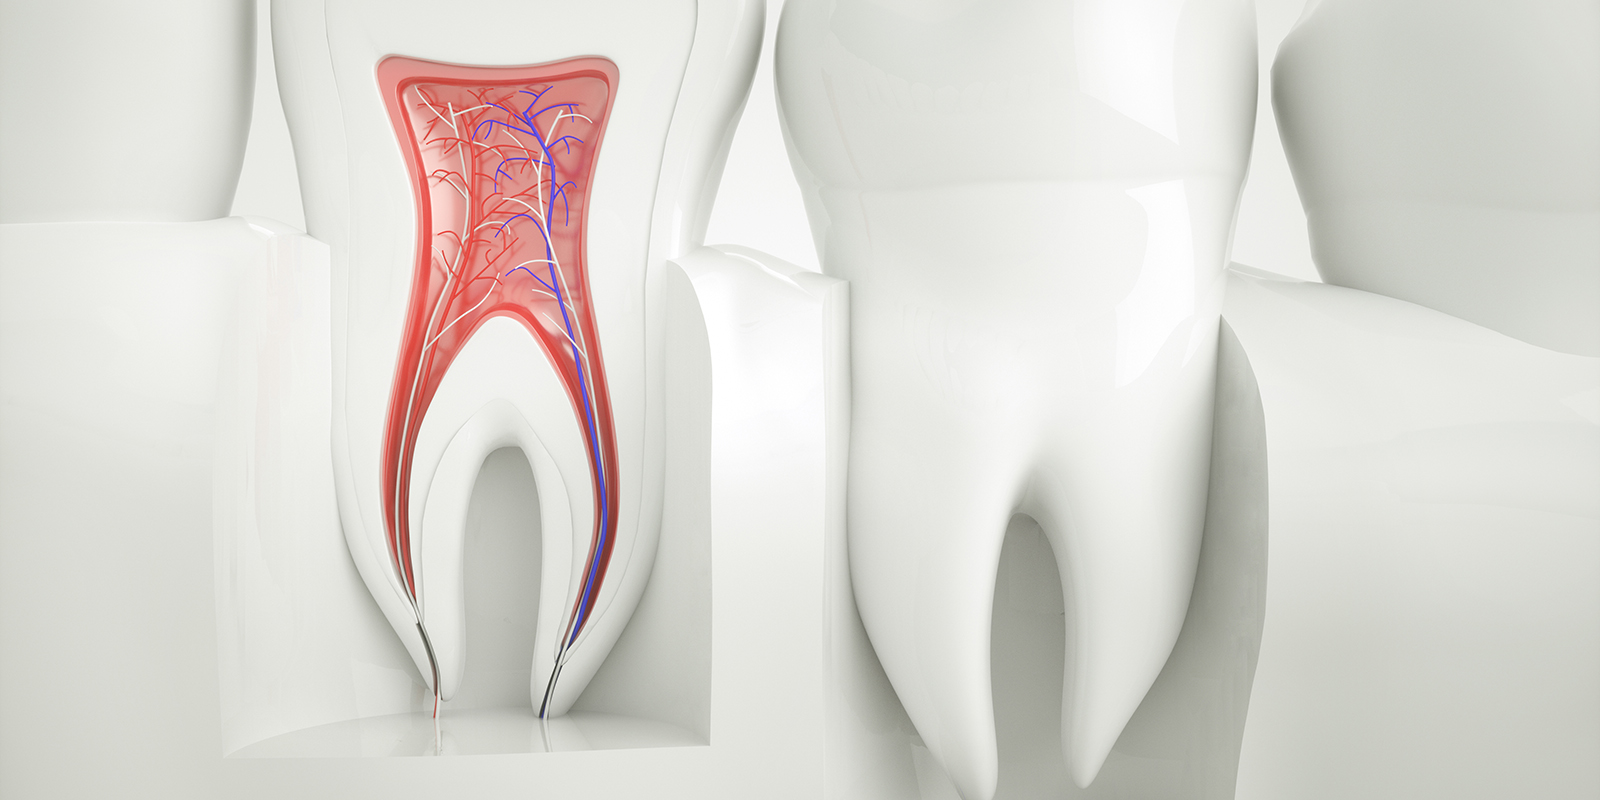

むし歯の進行・歯の破折・知覚過敏・かみ合わせ不良等により、歯の神経に刺激が加わっていると痛みがでます。冷たいものがキーンとしみたり、なにもしていなくても痛みがでることもあります。

痛みの原因と症状について

1:歯の神経に刺激が加わっているとき

2:歯の神経の先に膿がたまっているとき

むし歯の進行を放置したり、一度治療をした歯でも神経の穴の先で膿がたまると痛みがでます。膿は細菌の感染が原因です。ズキズキしたり、夜も眠れないほどの痛みになることもあります。